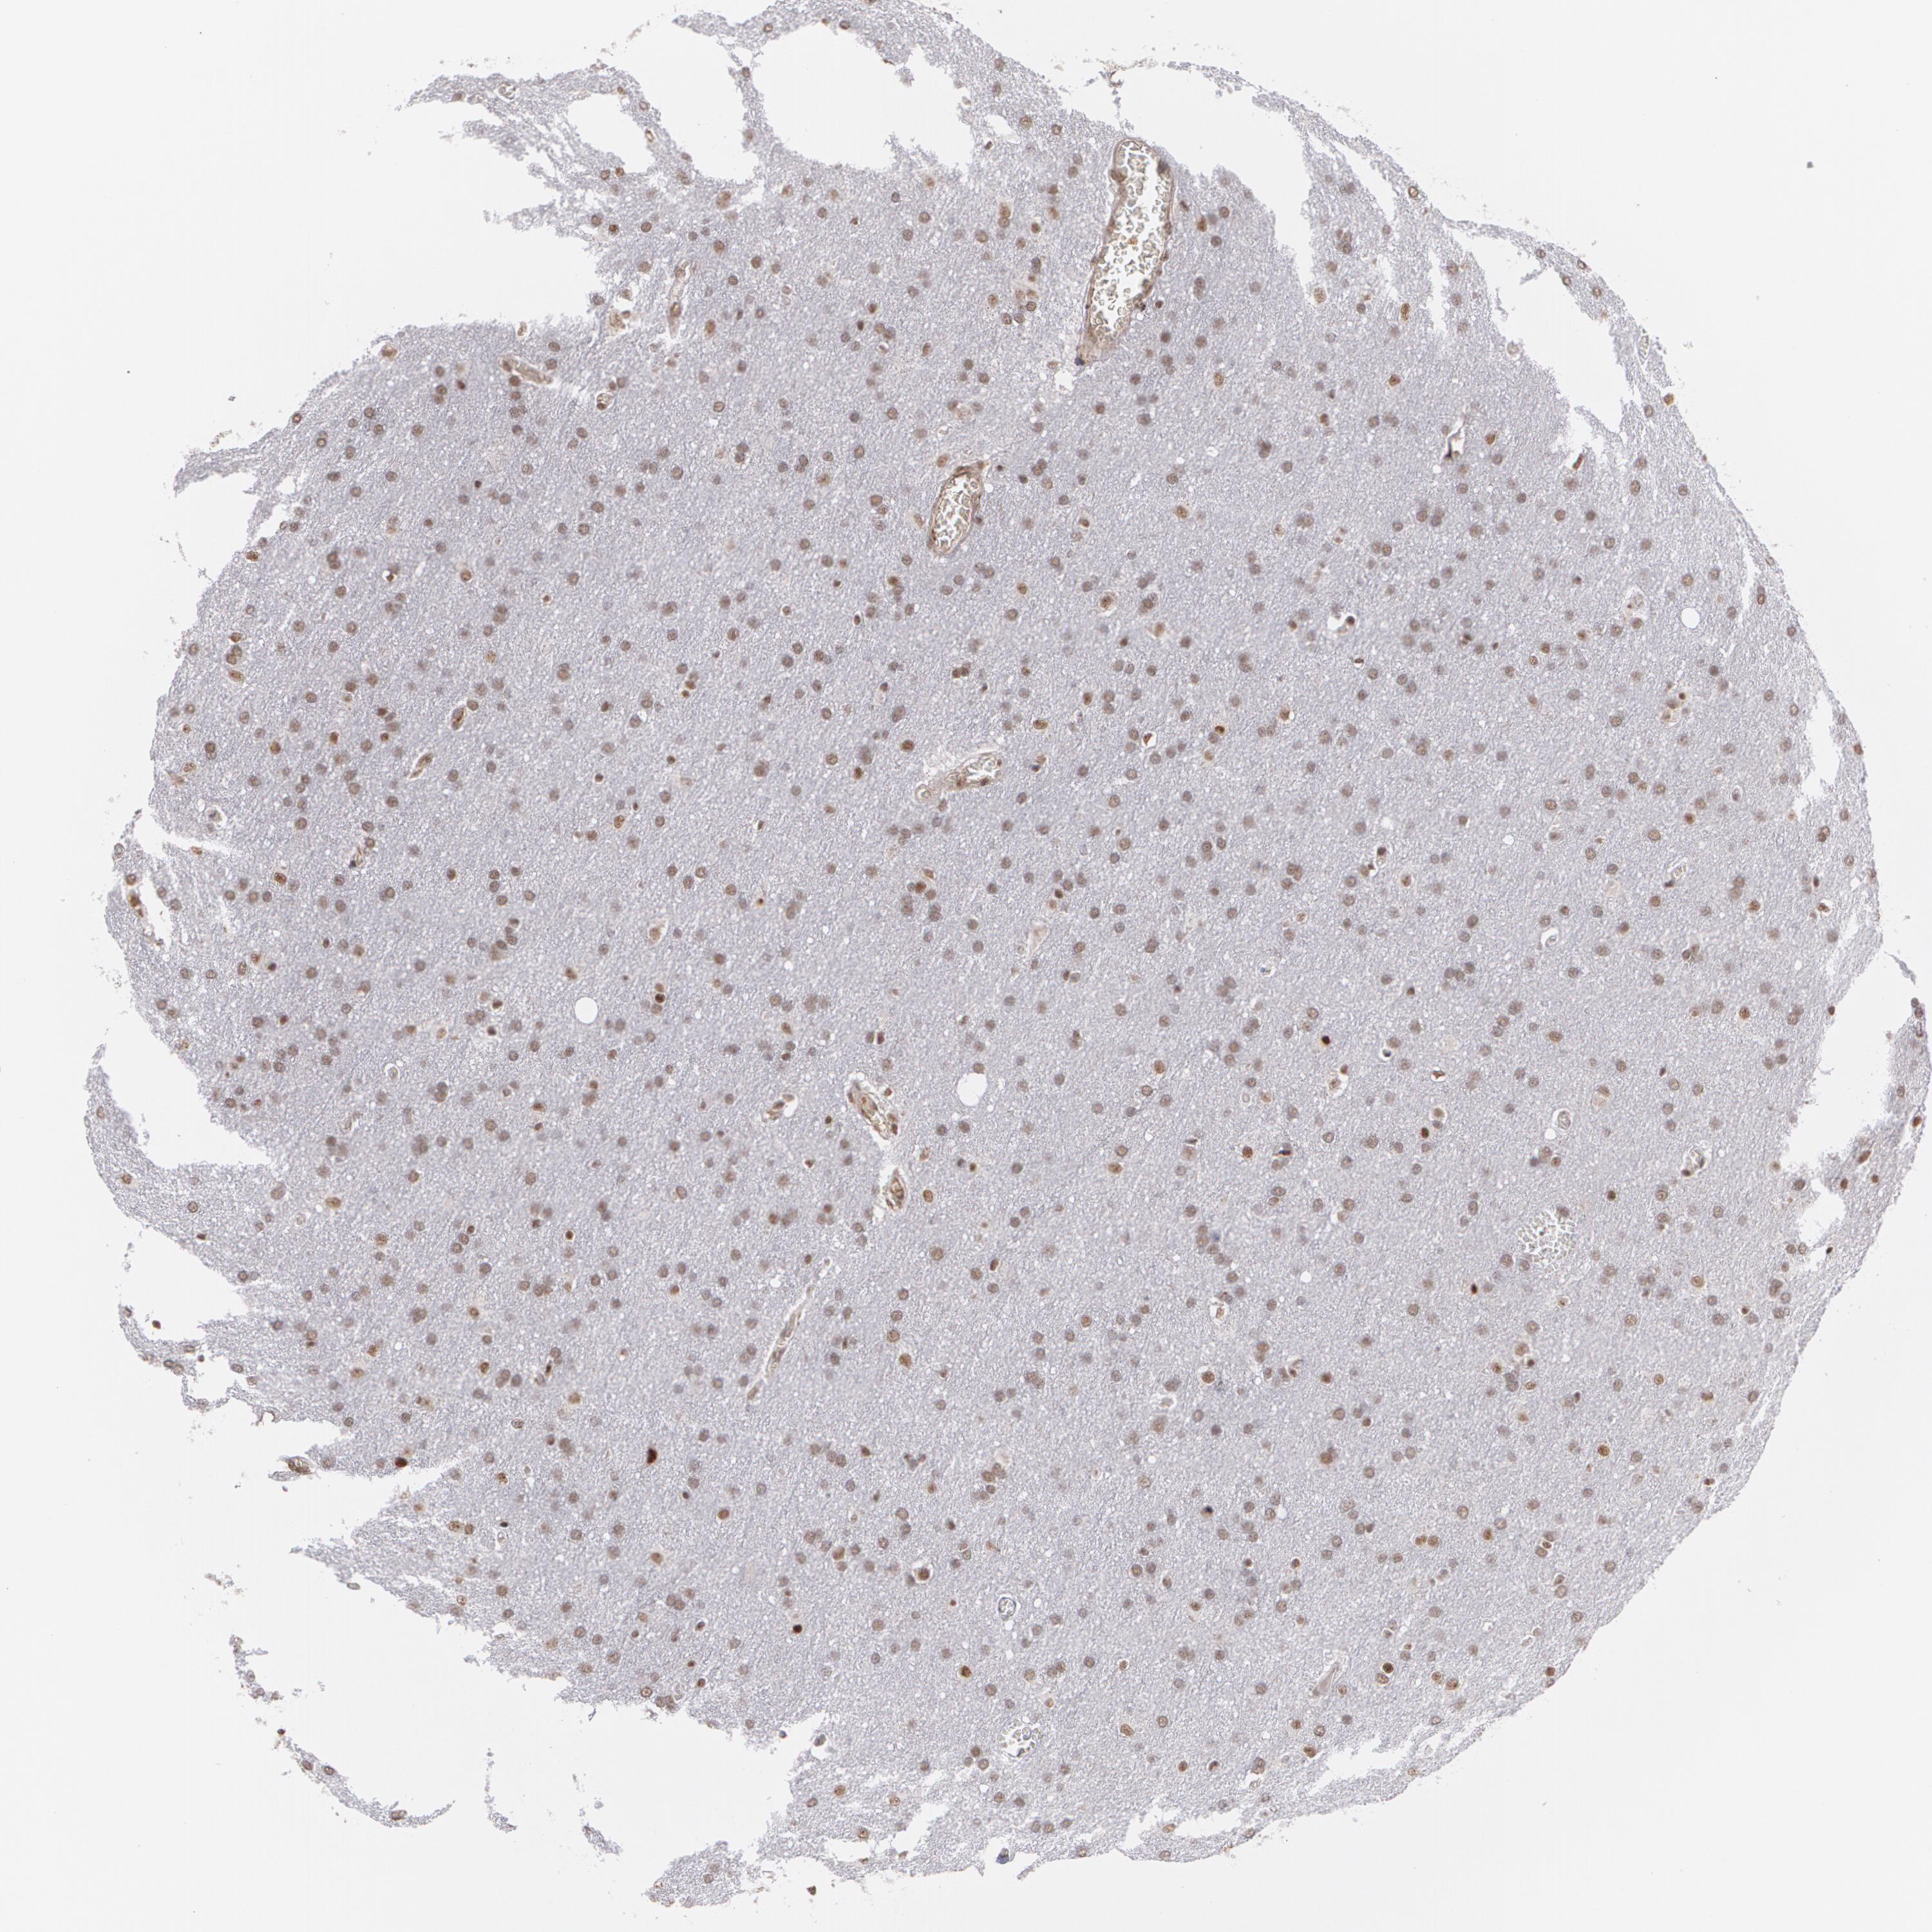

GLIOMA - Protein expressioni

A mouse-over function shows sample information and annotation data. Click on an image to view it in a full screen mode. Samples can be filtered based on level of antibody staining by selecting one or several of the following categories: high, medium, low and not detected. The assay and annotation is described here.

Note that samples used for immunohistochemistry by the Human Protein Atlas do not correspond to samples in the TCGA dataset.

Antibody stainingi

Antibody staining in the annotated cell types in the current human tissue is reported as not detected, low, medium, or high, based on conventional immunohistochemistry profiling in selected tissues. This score is based on the combination of the staining intensity and fraction of stained cells.

Each image is clickable and will lead to virtual microscopy that enables deeper exploration of all samples and also displays staining intensity scores, fraction scores and subcellular localization as well as patient and tissue information for each sample.

Antibody HPA001664

Staining

High

Medium

Low

Not detected

Intensity

Strong

Moderate

Weak

Negative

Quantity

>75%

75%-25%

<25%

None

Location

Nuclear

Cytoplasmic/membranous

Cytoplasmic/membranous,nuclear

Glioma, malignant, High grade

Glioma, malignant, NOS

Glioma, malignant, Low grade